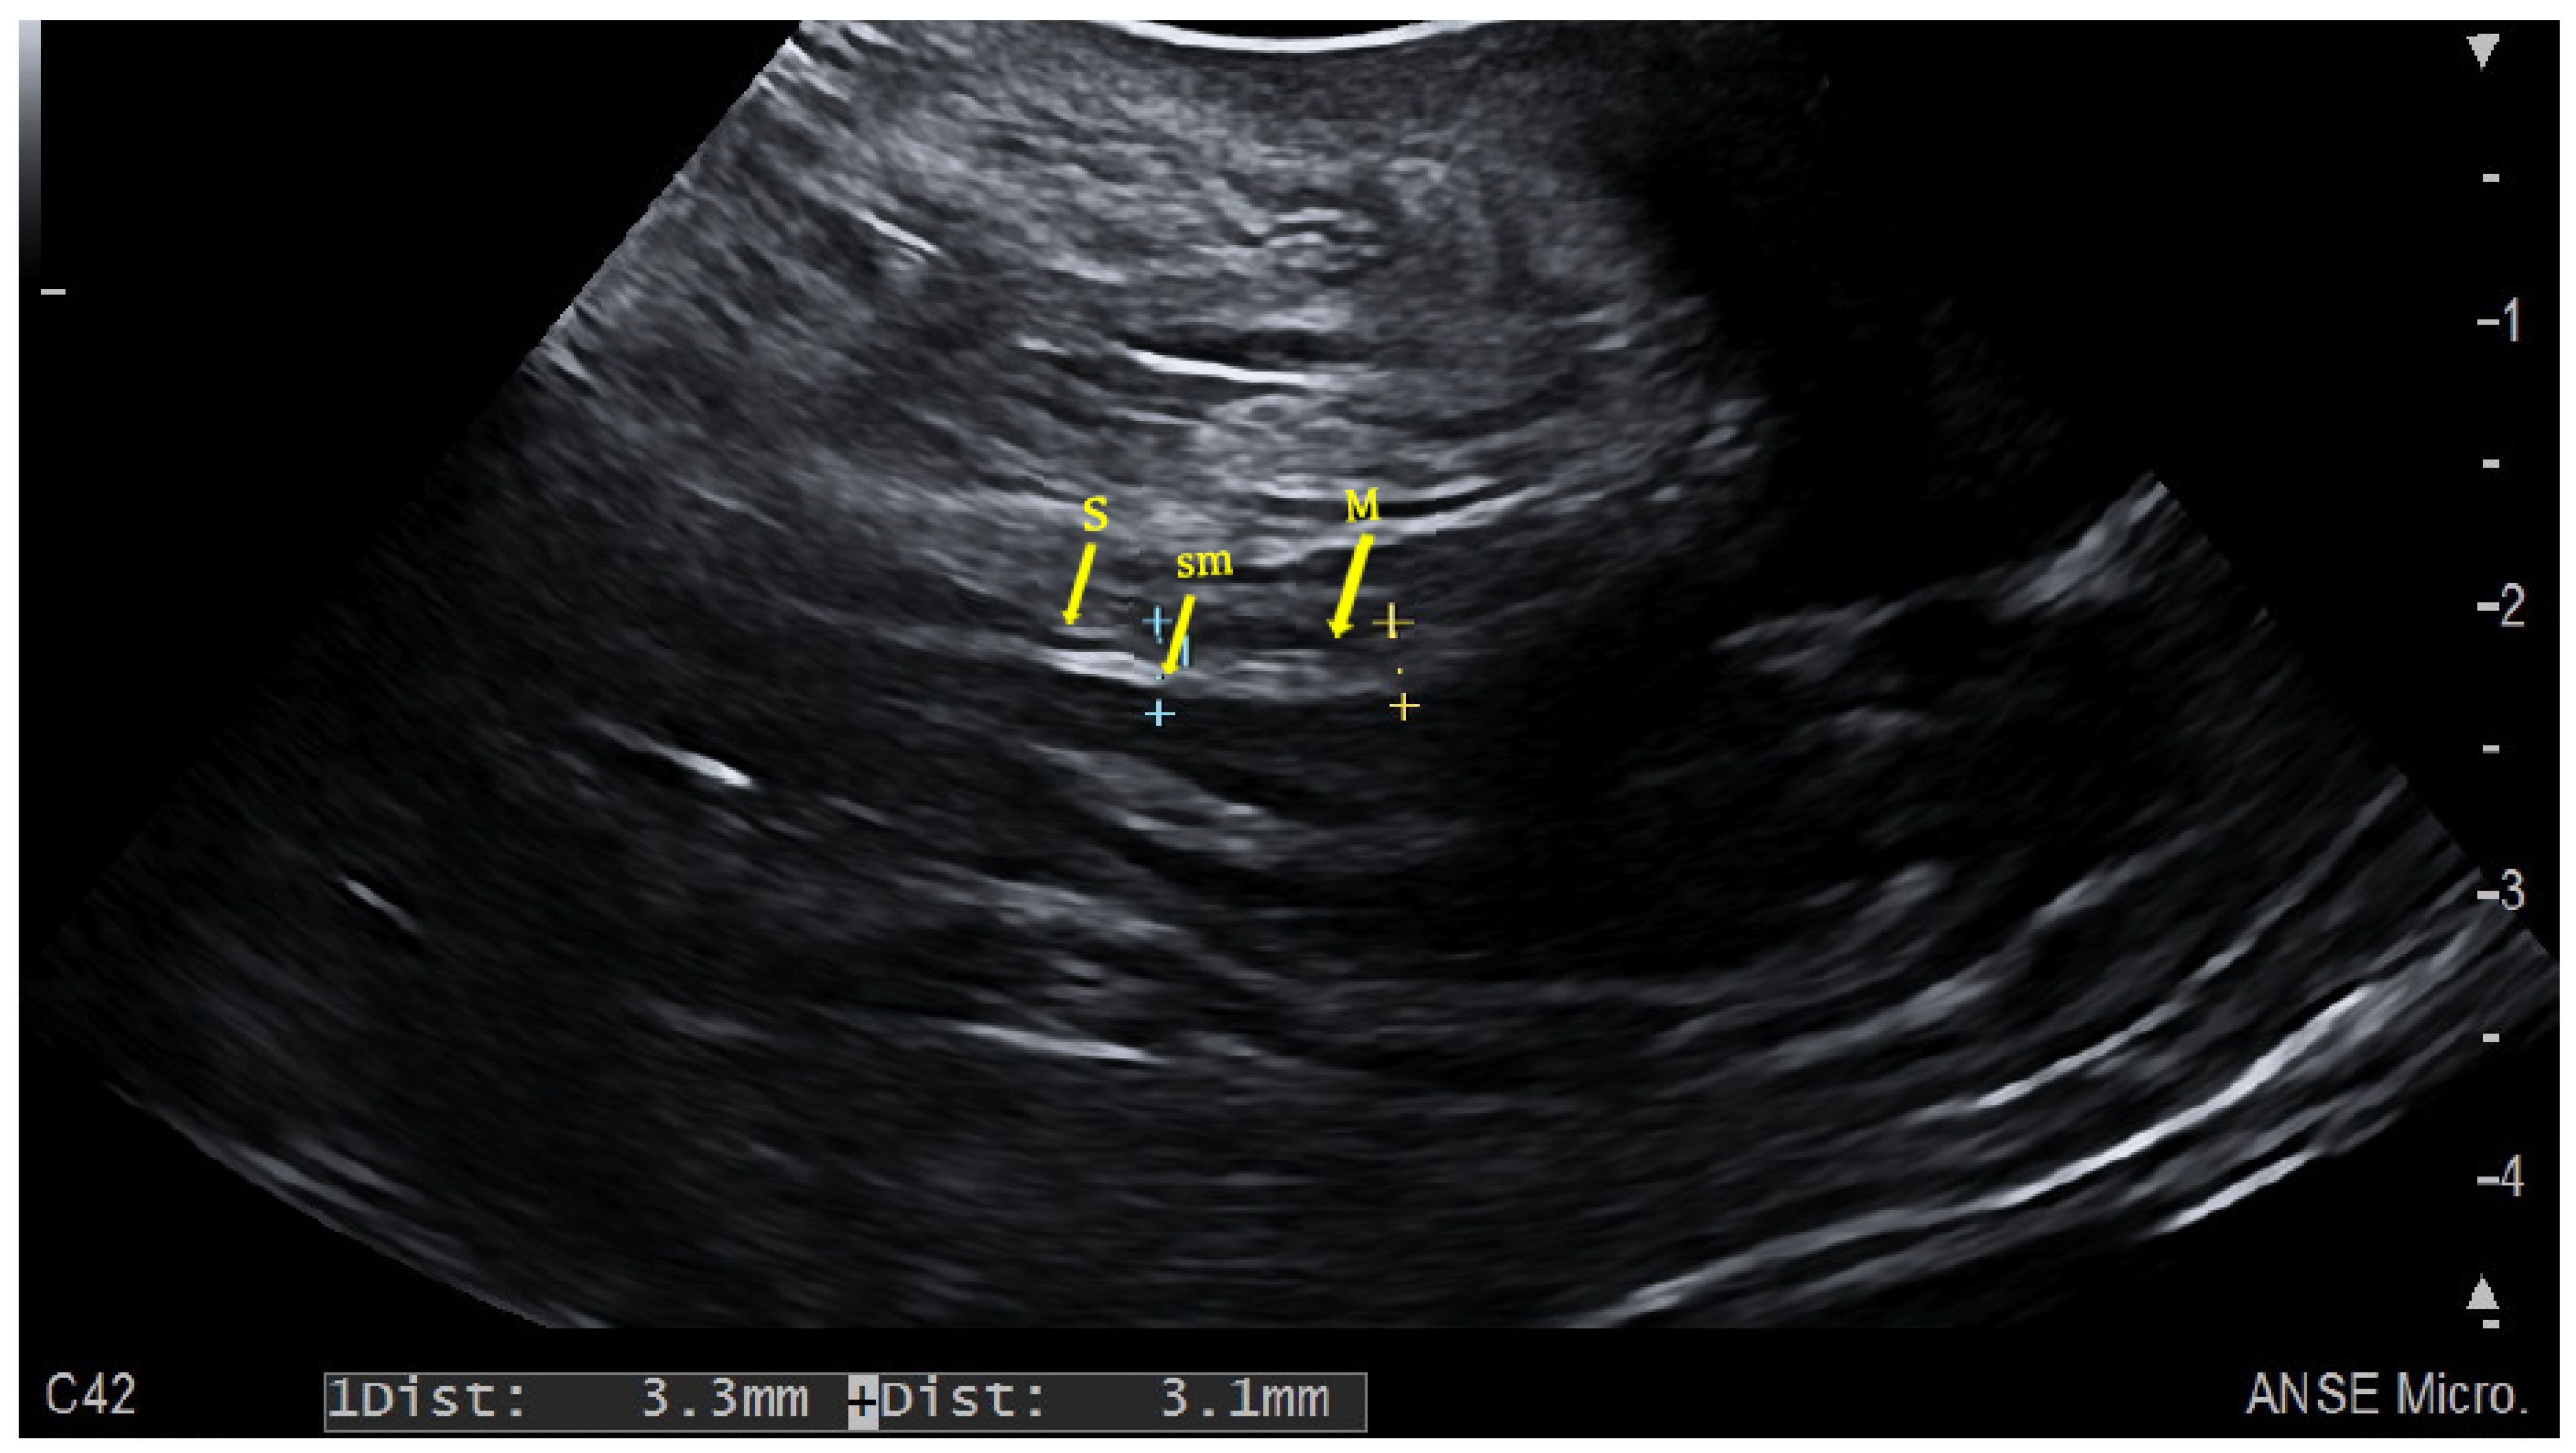

2.1. Colonic Evaluation

2.2. The Challenge of Rectum Evaluation